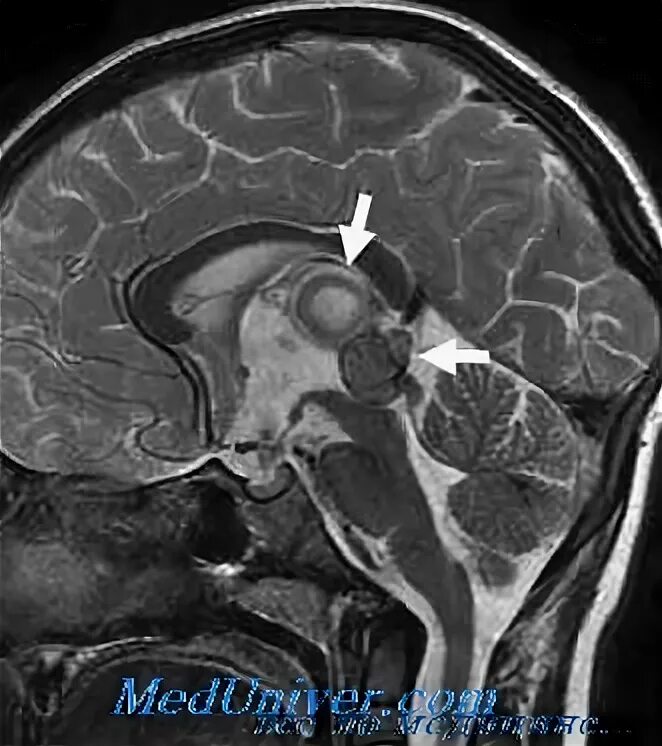

Симптомы кисты эпифиза